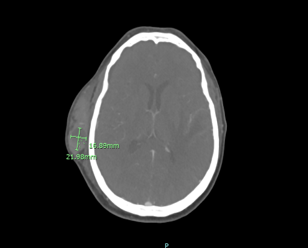

Upon arrival, CT of the head showed a large right frontotemporal scalp hematoma with hematocrit levels suggesting recent/active hemorrhage, no acute intracranial hemorrhage or extra axial collection, and left temporal encephalomalacia and gliosis likely related to prior treatment/ischemic insult with superimposed acute ischemia. CTA of the head/neck showed patent intracranial arteries without significant stenosis, occlusion, or aneurysm, a small amount of internal cerebral venous drainage, and a large superficial scalp hematoma over the right frontotemporal bone with active extravasation from the right superficial temporal artery. Both right and left internal carotid arteries showed no hemodynamically significant stenosis by NASCET criteria.

Image 2: CT Head Angiogram. Large superficial scalp hematoma over the right frontotemporal bone with active extravasation from the right superficial temporal artery 2.3 cm x 1.7cm